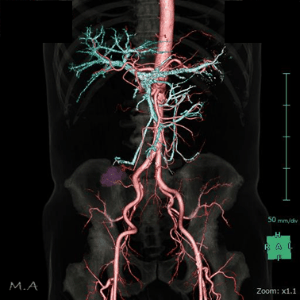

CT

当院ではGEヘルスケア製Revolution Maximaを設置しています

CTはX線とコンピュータを用いて、体の内部を自由な角度の断面で画像化できる検査で、頭部・胸部・腹部に加え、血流や骨などの詳細な情報を得ることができます。CTの高精度な画像を診断に用いることは、様々な病気の早期発見や治療後の経過観察に役立っています。検査は短時間で終了するため、患者様の負担も少ないです。また、実際の撮影したデータの統計を元にして、当院で行われた検査の被ばく線量が適正であることを年に2回検討し、線量低減対策に取り組んでいます。